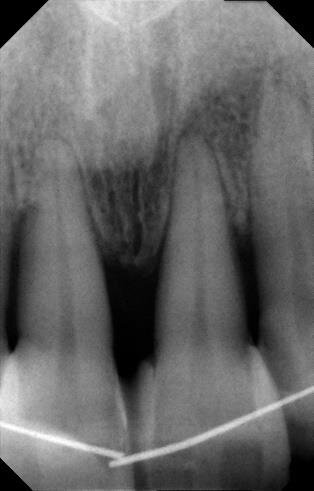

Tutto ciò viene dettagliatamente spiegato sia verbalmente, sia descritto nel “Consenso informato” che la paziente sottoscrive dopo aver richiesto un secondo consulto presso un altro studio. Il trattamento estrusivo dei due incisivi laterali inizia nel gennaio 2011 (Figg. 7, 8). Al raggiungimento del risultato desiderato (Figg. 9, 10), si attendono 60 giorni di “stabilizzazione” dell’osso alveolare18 (Figg. 11, 12).

La fase chirurgica viene pianificata con la preparazione iniziale (igiene orale, controllo emato-chimico delle condizioni della paziente, prescrizione della profilassi/terapia antibiotica19-20 e della sospensione del fumo). Il 23 giugno 2011, vengono estratti i due incisivi laterali (Figg. 13, 14) e inseriti contestualmente due impianti Xive (Dentsply) di diametro 3,8 mm e lunghezza 15 mm (Figg. 15, 16), dimensioni ottimali per la successiva protesi (ponte di 4 elementi da 1.2 a 2.2 con 1.1 e 2.1, elementi “intermedi”).